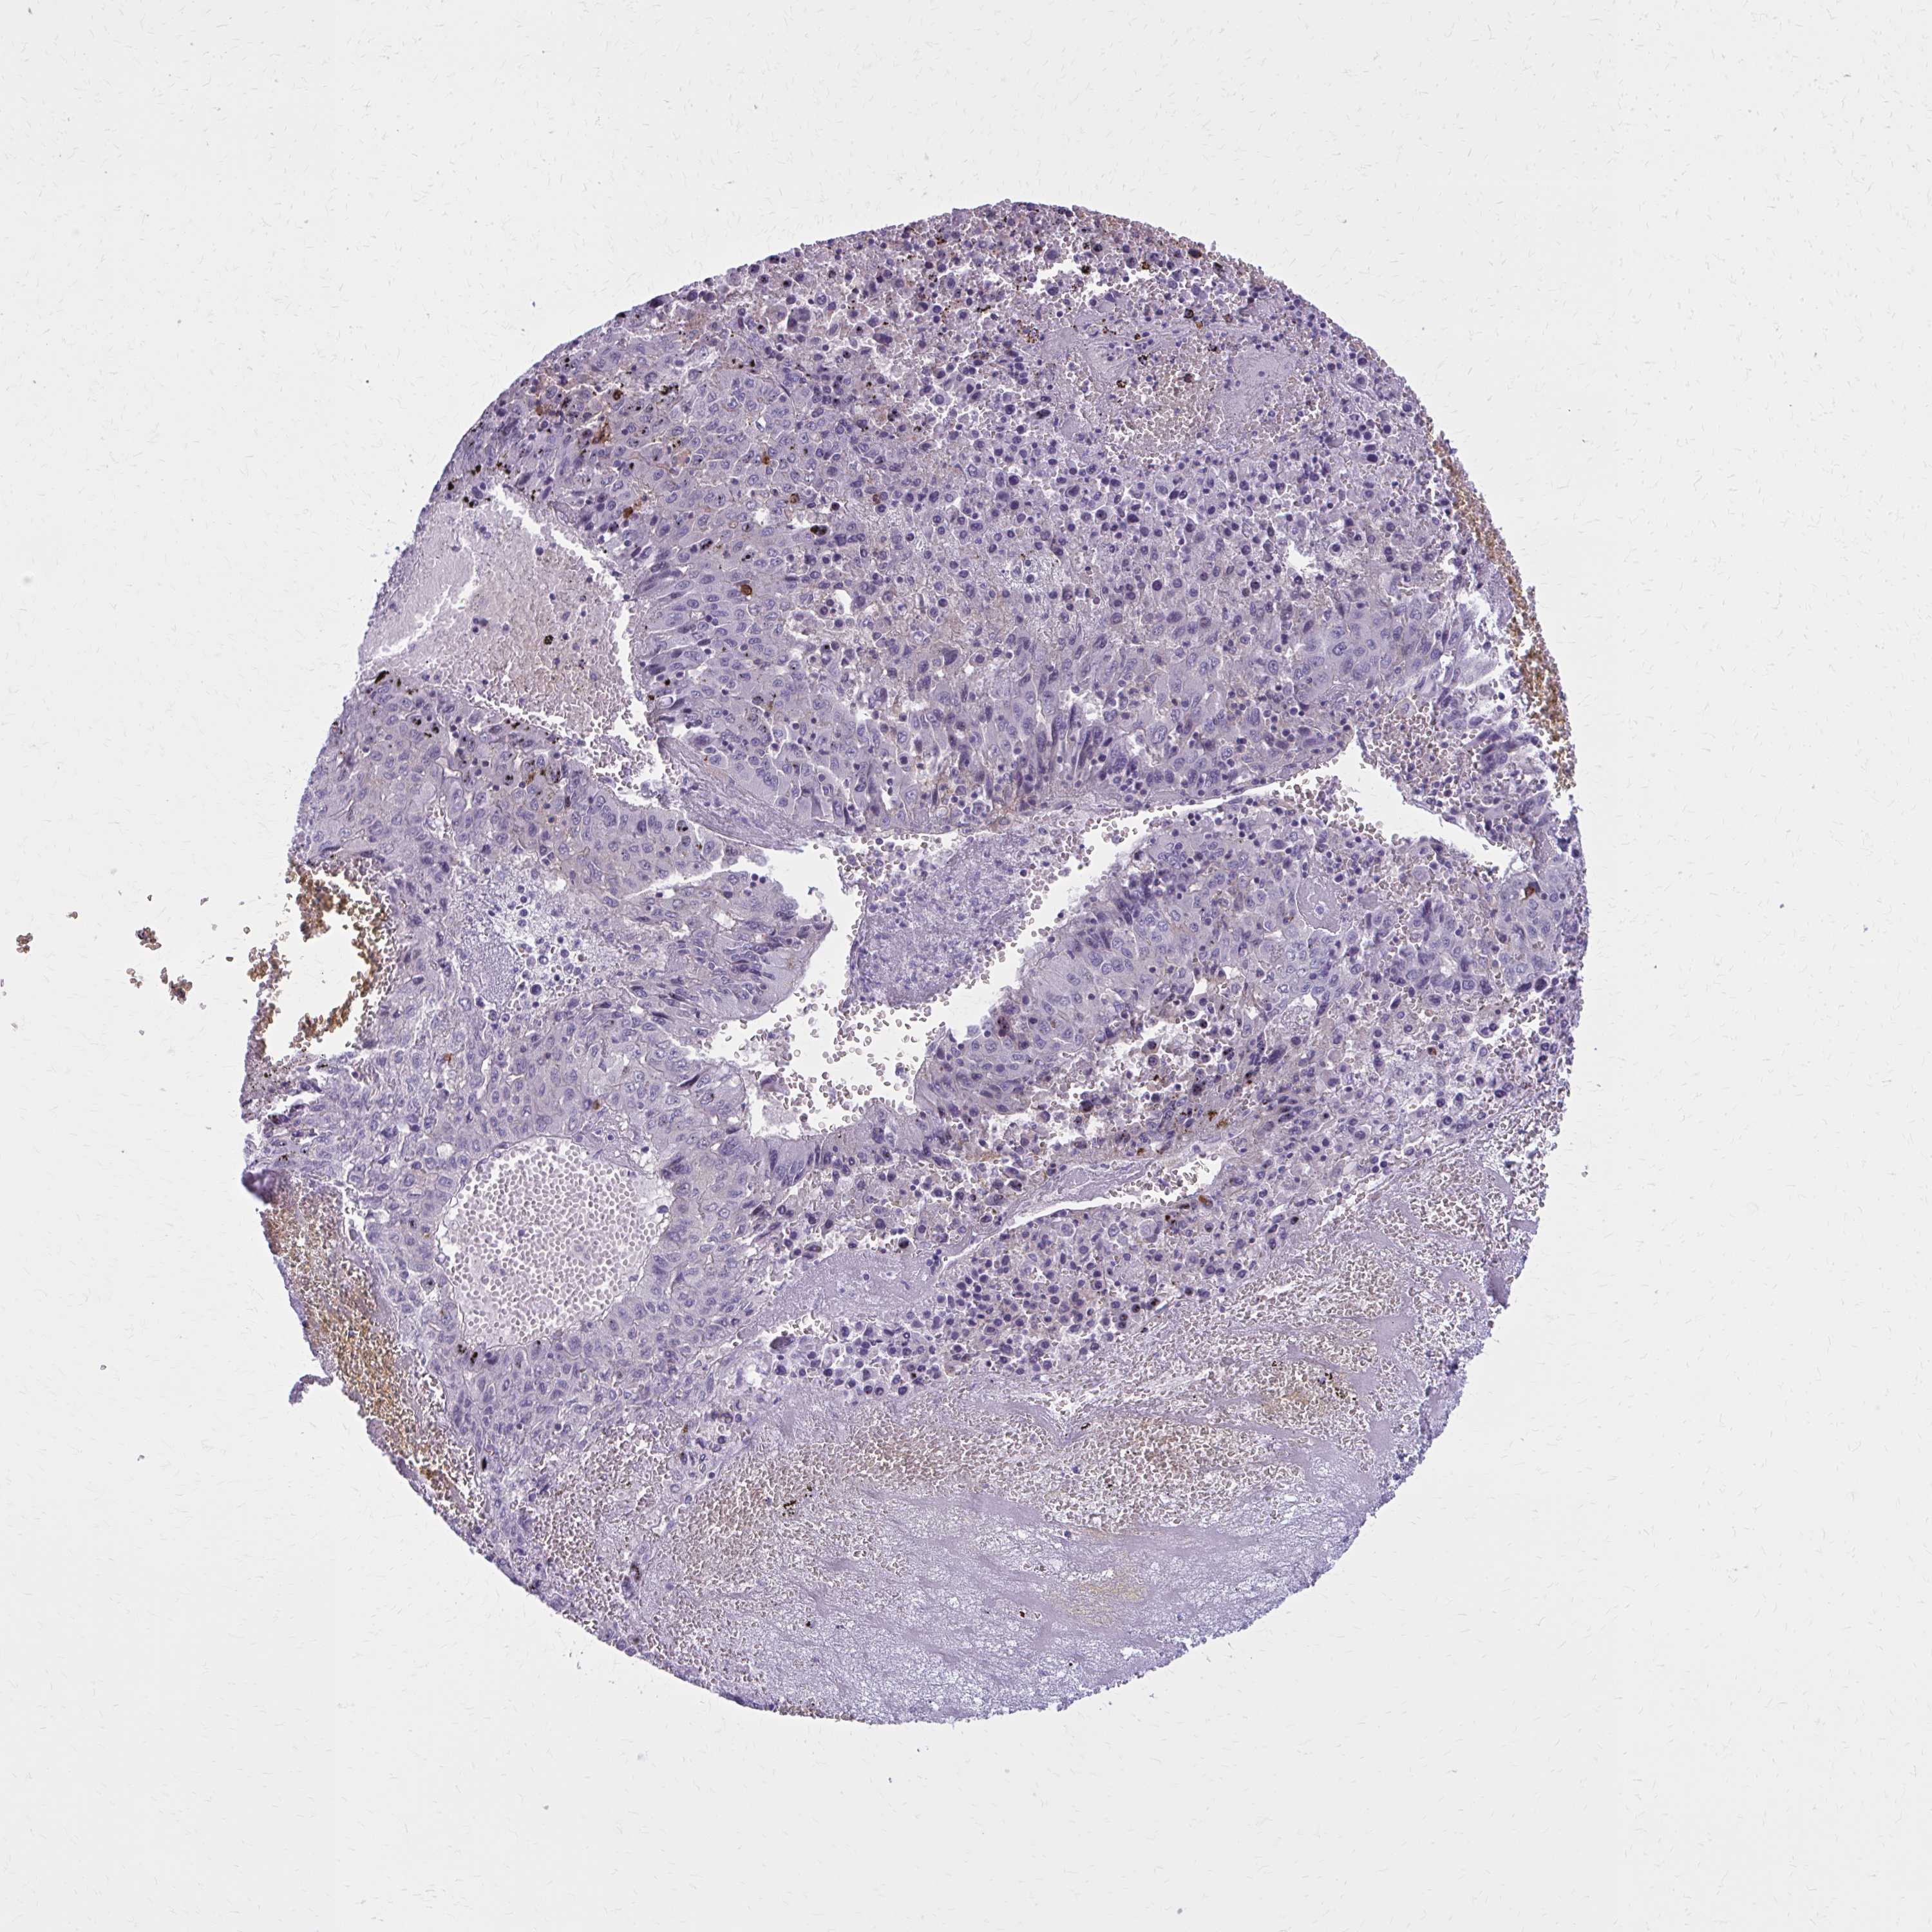

LIVER CANCER - Protein expressioni

A mouse-over function shows sample information and annotation data. Click on an image to view it in a full screen mode. Samples can be filtered based on level of antibody staining by selecting one or several of the following categories: high, medium, low and not detected. The assay and annotation is described here.

Note that samples used for immunohistochemistry by the Human Protein Atlas do not correspond to samples in the TCGA dataset.

Antibody stainingi

Antibody staining in the annotated cell types in the current human tissue is reported as not detected, low, medium, or high, based on conventional immunohistochemistry profiling in selected tissues. This score is based on the combination of the staining intensity and fraction of stained cells.

Each image is clickable and will lead to virtual microscopy that enables deeper exploration of all samples and also displays staining intensity scores, fraction scores and subcellular localization as well as patient and tissue information for each sample.

Antibody HPA022132

Antibody HPA052381

Antibody CAB002493

Antibody CAB025255

Cholangiocarcinoma

Carcinoma, Hepatocellular, NOS